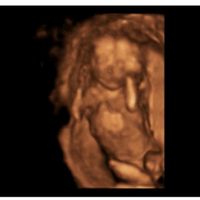

Hola a todas! Hace muchísimo que no me paso por aquí… en 2020 me quedé embarazada por IA y ahora hemos vuelto a la carga. La primera IA fue negativa (aunque a 12 días post ovitrelle se me marcaba el...